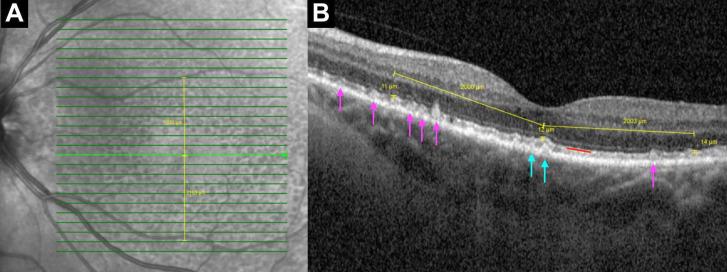

Post hoc analysis of a cross-sectional study. 165 AMD subjects (aged 51-100; 61% women). Spectral-domain optical coherence tomography was obtained in both eyes. Masked readers assigned subjects to three groups: drusen only, SDD+drusen (SDD+D) and SDD only. EZ thickness was measured subfoveally and 2000 µm nasally, temporally, superiorly and inferiorly from the fovea. Univariate testing was performed using two-tailed t-tests with Bonferroni correction.

对一项横断面研究进行了事后分析。165 名 AMD 患者(年龄 51-100 岁;61%为女性)。对双眼进行了频域光学相干断层扫描。盲法读者将患者分为三组:仅存在玻璃膜疣、存在 SDD+玻璃膜疣(SDD+D)和仅存在 SDD。在黄斑下和距黄斑 2000μm 的鼻侧、颞侧、上侧和下侧测量 EZ 厚度。使用双侧 t 检验和 Bonferroni 校正进行单变量检验。